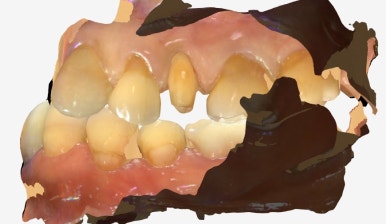

오늘은 오래 사용하던 크라운이 깨져 내원하신 환자분께

지르코니아 재보철을 하루 만에 진행한 사례를 소개해드릴게요.

이번 환자분 역시 기존 크라운이 레진계열 소재로 제작돼

시간이 지나면서 파절된 상태였습니다.